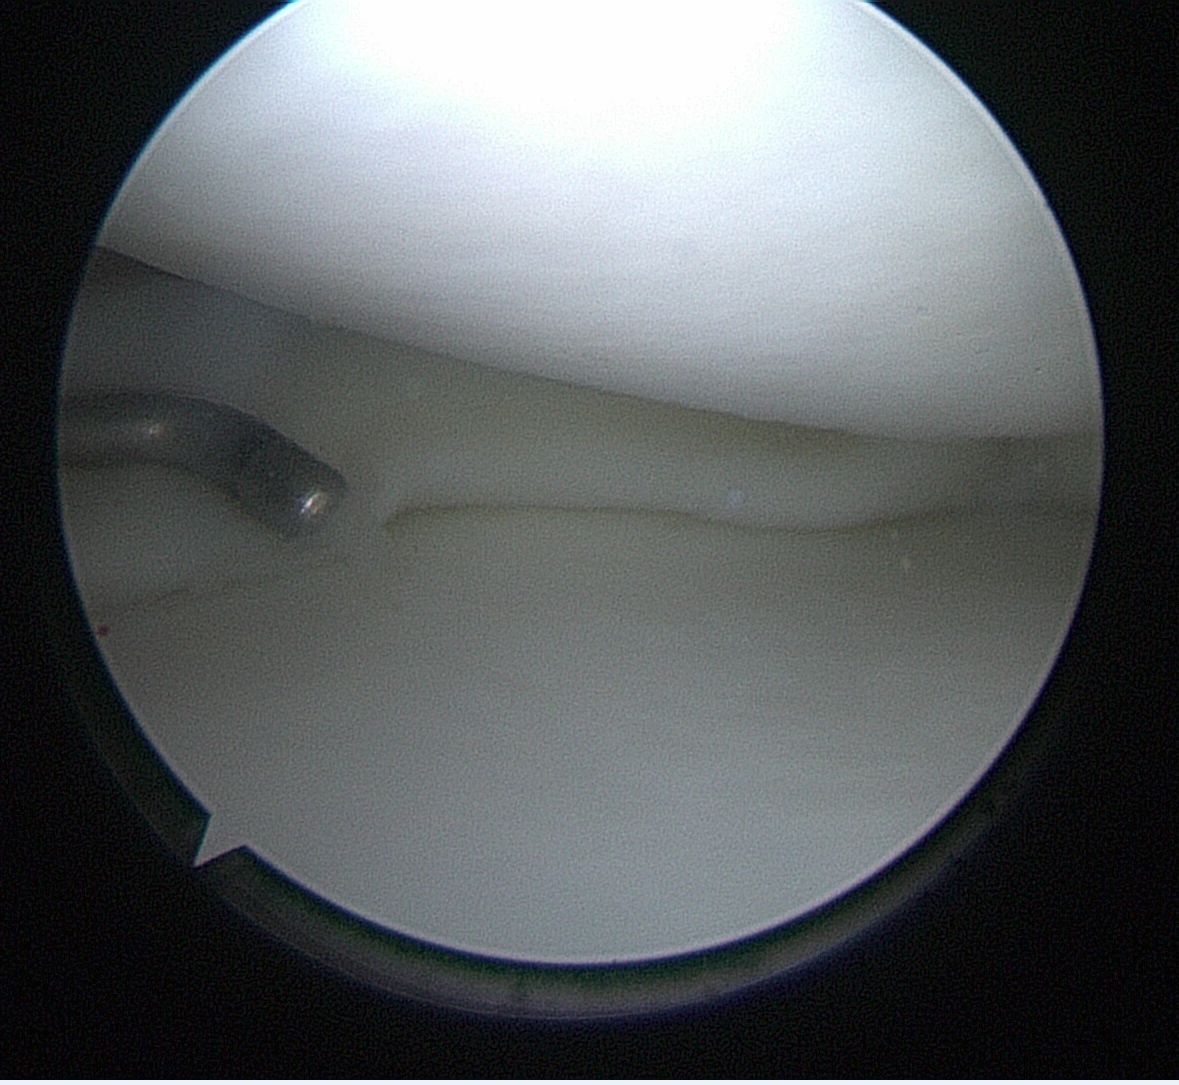

- Meniscus Surgery

- Meniscus Surgery 2